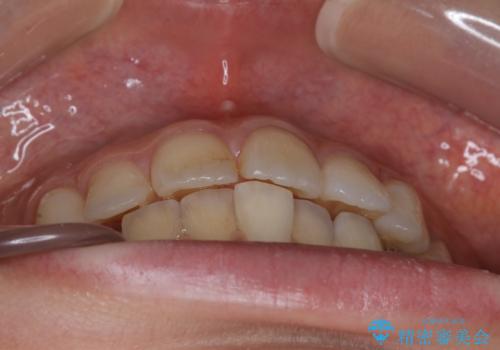

前歯のガタつきを改善 抜歯矯正後の後戻り

- 抜歯矯正後の後戻りで前歯ガタつきが主訴で来院された患者様です。

後戻り矯正や非抜歯矯正はインビザラインをご案内する事が多いですが、自己管理の煩わしさから、目立たないワイヤー装置にて矯正治療を行うこととしました。

後戻りの程度としては軽度なので、治療期間としては短く終えることが出来ました。

前歯の正中線も改善され大変満足して頂きました。